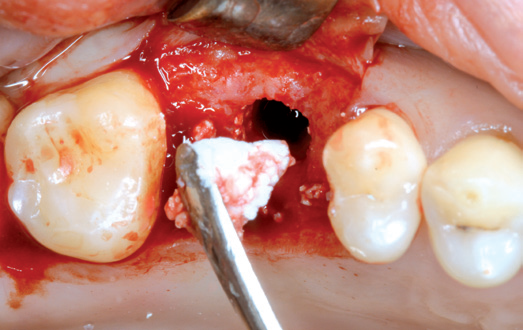

06/10 - Insertion of maxresorb® inject for internal sinus liftInternal sinus lift with maxresorb® inject - case Dr. Frank Kistler

07/10 - Augmentation of the sinus floor by a crestal approachInternal sinus lift with maxresorb® inject - case Dr. Frank Kistler

08/10 - Insertion of maxresorb® inject with bone condenserInternal sinus lift with maxresorb® inject - case Dr. Frank Kistler